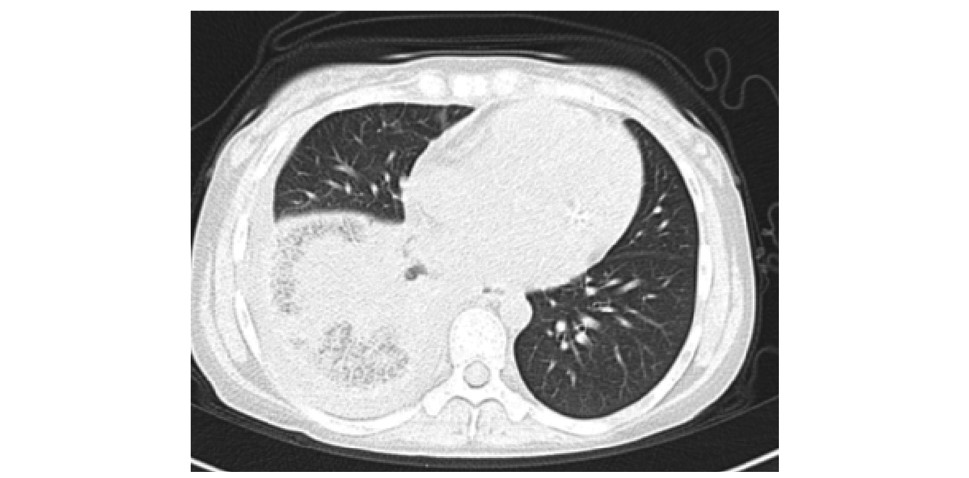

摘要: 心腔内血栓形成是系统性红斑狼疮(systemic lupus erythematosus,SLE)继发抗磷脂综合征(antiphospholipid syndrome,APS)的罕见并发症,治疗难度极大。本文报道1例SLE合并心内血栓、肺栓塞病例,病情复杂,猝死风险高,血栓和出血状态下的抗凝选择、感染状态下的原发病评估和治疗均较为棘手。经过多学科诊疗,在内科积极治疗的基础上,创造手术条件并选择恰当时机完成手术治疗,病情得到有效控制。Abstract: Intracardiac thrombus is a rare complication of Antiphospholipid syndrome secondary to systemic lupus erythematosus (SLE). Its treatment is extremely tough and requires a multidisciplinary approach. We reported a case of SLE with intracardiac thrombus and pulmonary embolism. The patient was complicated with hemoptysis and kidney injury, and had a high risk of sudden death from incidental thrombus shedding off. In the state of thrombosis and hemorrhage, the management of anticoagulation and the evaluation and treatment of the primary disease complicated with infection are challenging. The multidisciplinary collaboration helpedus to create a more favorable surgical condition while controlling SLE aggressively. After surgical treatment at the proper time, the outcome of the patient was satisfying.